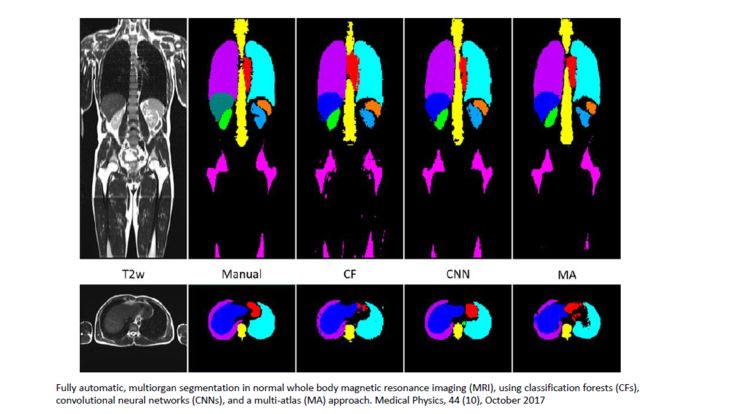

这是2017年Medical physics上的一篇文章,它做了全身的大量器官的自动识别和分割,并且通过三种算法的比较,得出结论说CNN是最好的一种算法,分割效率相对最高。

文章把人体器官分成几大类,比如说左肺,右肺,肝脏和肾脏等等,还计算一下它们的符合度和相似度,并且总结了算法的相对优势和劣势,值得学习和借鉴。